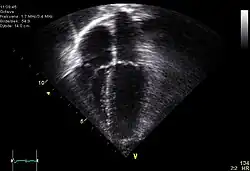

Ecocardiografía

Se utiliza para crear imágenes del corazón que son más detalladas que las imágenes obtenidas por una radiografía simple. Se pueden obtener imágenes en tiempo real en dos o tres dimensiones. Permite evaluar el funcionamiento de las válvulas cardíacas, para el diagnóstico de estenosis o insuficiencia, y para evaluar la contracción del músculo cardíaco, para el diagnóstico de hipertrofia o dilatación de los ventrículos y aurículas.

Se puede hacer una ecocardiografía de esfuerzo para comprobar el funcionamiento del miocardio para bombear la sangre al cuerpo. Se utiliza para detectar una disminución en el flujo sanguíneo al corazón, producido por un estrechamiento de las arterias coronarias.[17]